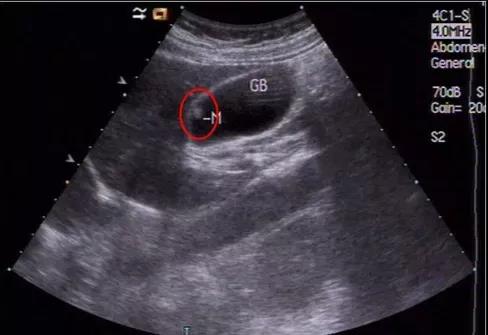

①看真假:真正可能變癌的是真息肉,假息肉不用管;